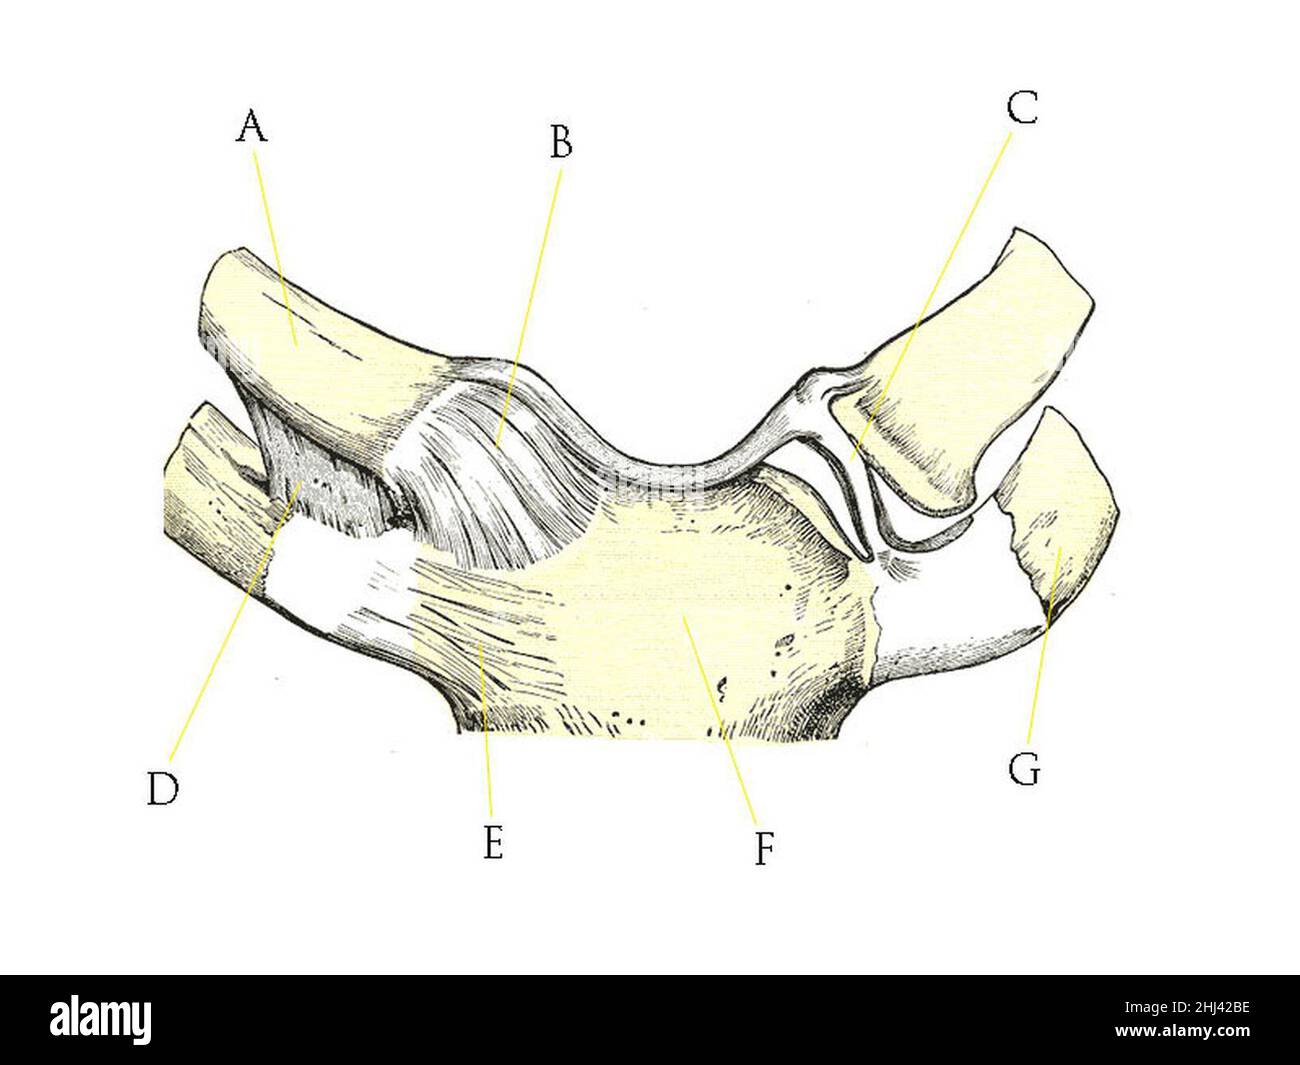

RF3CM31GP–3D-Illustrationskonzept der Anatomie der Knochengelenke der oberen Extremitäten des menschlichen Skelettsystems

RF3CM2YY5–3D-Illustrationskonzept der Anatomie der Knochengelenke der oberen Extremitäten des menschlichen Skelettsystems